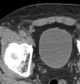

A hernia is the abnormal exit of tissue or an organ, such as the bowel, through the wall of the cavity in which it normally resides. Hernias come in a number of types. [Source: Wikipedia ]